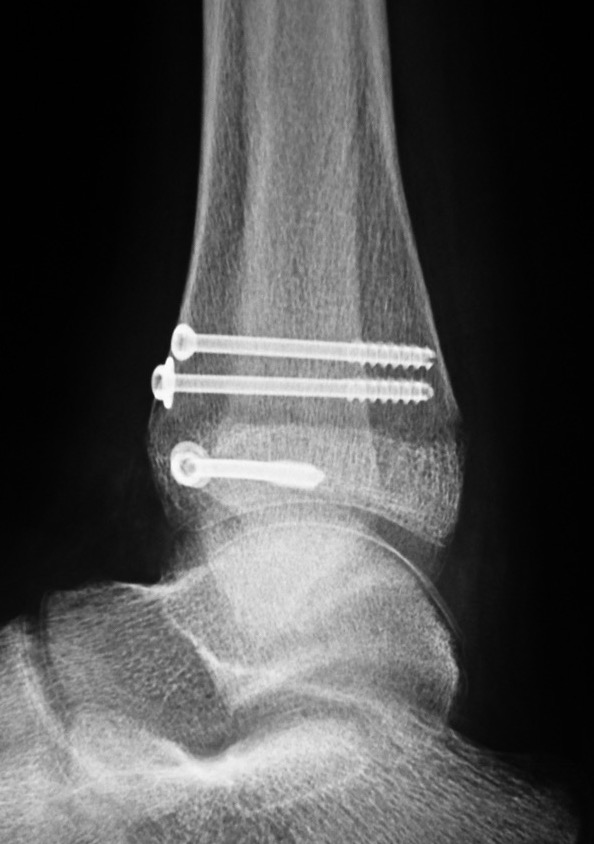

Operative management

Indication

Displaced articular fracture > 2 mm

Technique

AO surgery reference triplanar fixation

JBJS Essential surgical technique triplanar fixation video

Anterior approach between EHL and EDL

- reduce fracture with large reduction forceps

- epiphyseal screw from lateral to medial / medial to lateral

- metaphyseal AP screw into Thurston-Holland fragment

Results

- systematic review of 830 adolescent triplanar fractures

- average age 13

- 17% associated fibular fractures

- premature growth closure / leg length discrepancy 1%